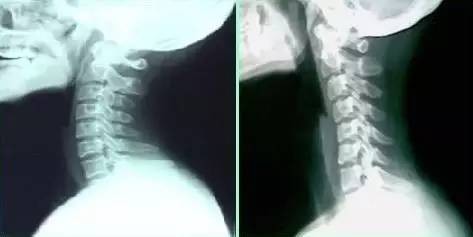

10)Gloriaaaa__:有一次突然疼的不能低头,月初回国拍了片子医生说曲度反张,正常人的颈椎是往后倾的 我的是直直的(4个zan)

小编点评:听起来应该是这样滴?左边正常人,右边颈椎病患者